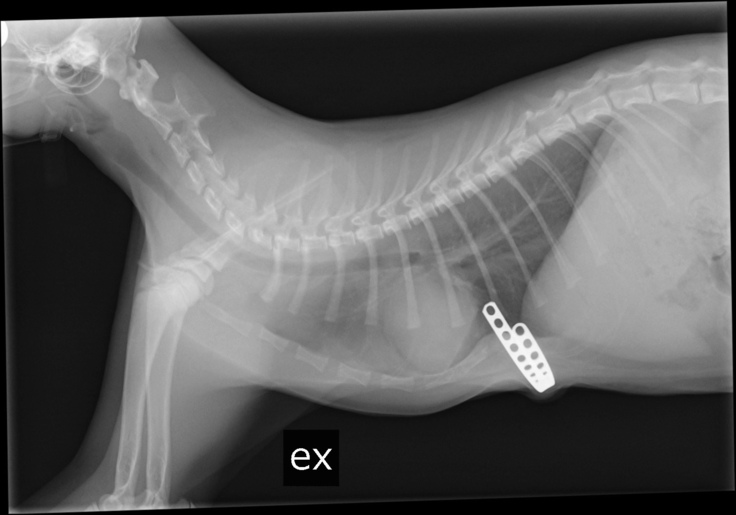

この写真は漏斗胸が発覚した際に撮影したレントゲン写真です